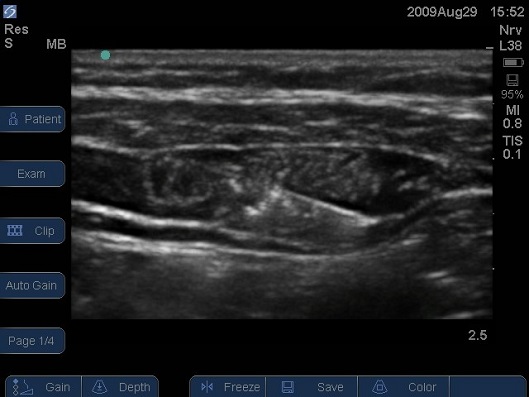

Figure 6 Ultrasound image of lateral abdominal wall of infant, needle inserted from anterior to posterior using an in plane needling technique. Note the spread of local anaesthetic between the inner most muscles. In small children it is common for the local anaesthetic to back track along the needle path as is seen here by the ‘fluffing’ of the interior oblique muscle.